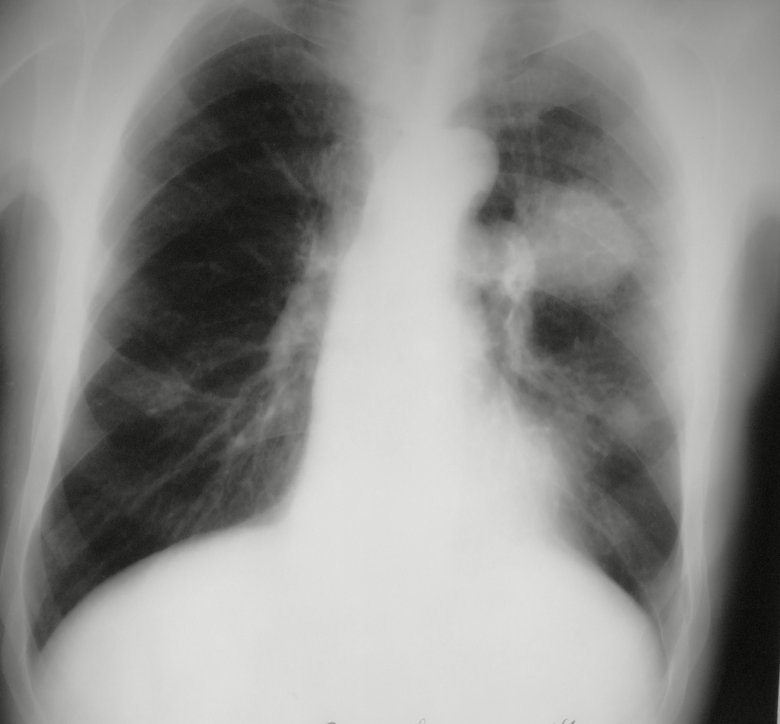

Периферический рак

Обсуждалось здесь viewtopic.php?f=24&t=867